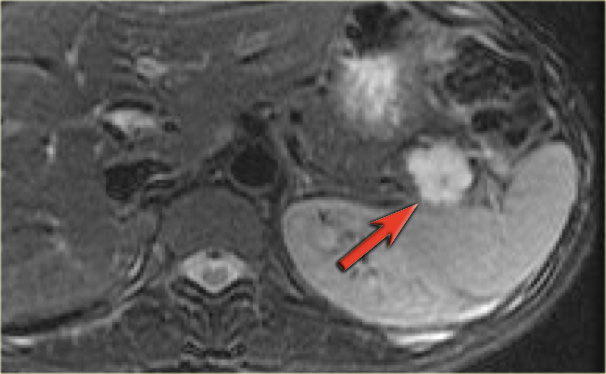

MRI will easily demonstrate the cystic nature of these lesions (fig).

The T2WI with fatsat nicely demonstrates a lobulated hyperintense lesion with central scar, which is characteristic of a SCN.